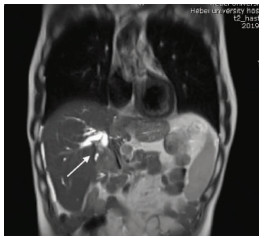

Multidisciplinary treatment of hepatocellular carcinoma with tumor thrombosis in the left portal vein: A case report

Jihong YANG, Guoxiang CHEN, Mo ZHOU, Jisen ZHAO, Yuan WANG, Yuanlong ZHOU

2021, 37(3): 666-679. DOI: 10.3969/j.issn.1001-5256.2021.03.031

Abstract(1185) HTML (567) PDF (3239KB)(69)

Abstract: